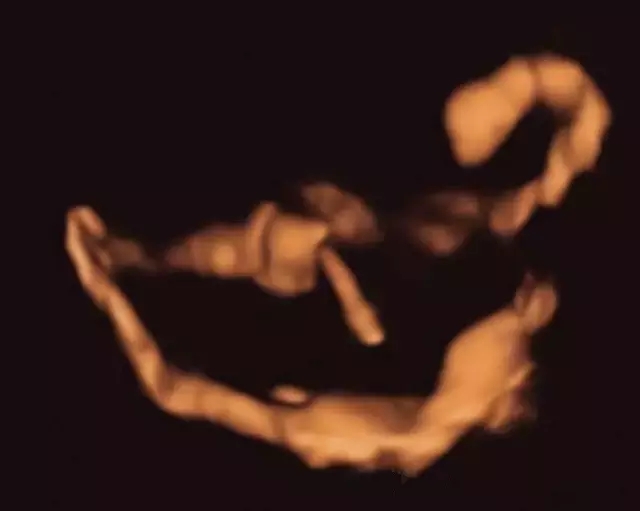

子宫输卵管超声造影实时动态图

左侧输卵管近端不通,右侧输卵管通畅(伴远端盘曲)